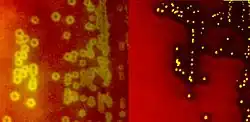

Species of streptococci are classified based on their hemolytic properties.[10] Alpha-hemolytic species cause oxidization of iron in hemoglobin molecules within red blood cells, giving it a greenish color on blood agar. Beta-hemolytic species cause complete rupture of red blood cells. On blood agar, this appears as wide areas clear of blood cells surrounding bacterial colonies. Gamma-hemolytic species cause no hemolysis.[11]

Beta-hemolysis (β-hemolysis), sometimes called complete hemolysis, is a complete lysis of red cells in the media around and under the colonies: the area appears lightened (yellow) and transparent. Streptolysin, an exotoxin, is the enzyme produced by the bacteria which causes the complete lysis of red blood cells. There are two types of streptolysin: Streptolysin O (SLO) and streptolysin S (SLS). Streptolysin O is an oxygen-sensitive cytotoxin, secreted by most group A Streptococcus (GAS), and interacts with cholesterol in the membrane of eukaryotic cells (mainly red and white blood cells, macrophages, and platelets), and usually results in beta-hemolysis under the surface of blood agar. Streptolysin S is an oxygen-stable cytotoxin also produced by most GAS strains which results in clearing on the surface of blood agar. SLS affects immune cells, including polymorphonuclear leukocytes and lymphocytes, and is thought to prevent the host immune system from clearing infection. Streptococcus pyogenes, or GAS, displays beta hemolysis.

Alpha-hemolytic S. viridans (right) and beta-hemolytic S. pyogenes (left) streptococci growing on blood agar